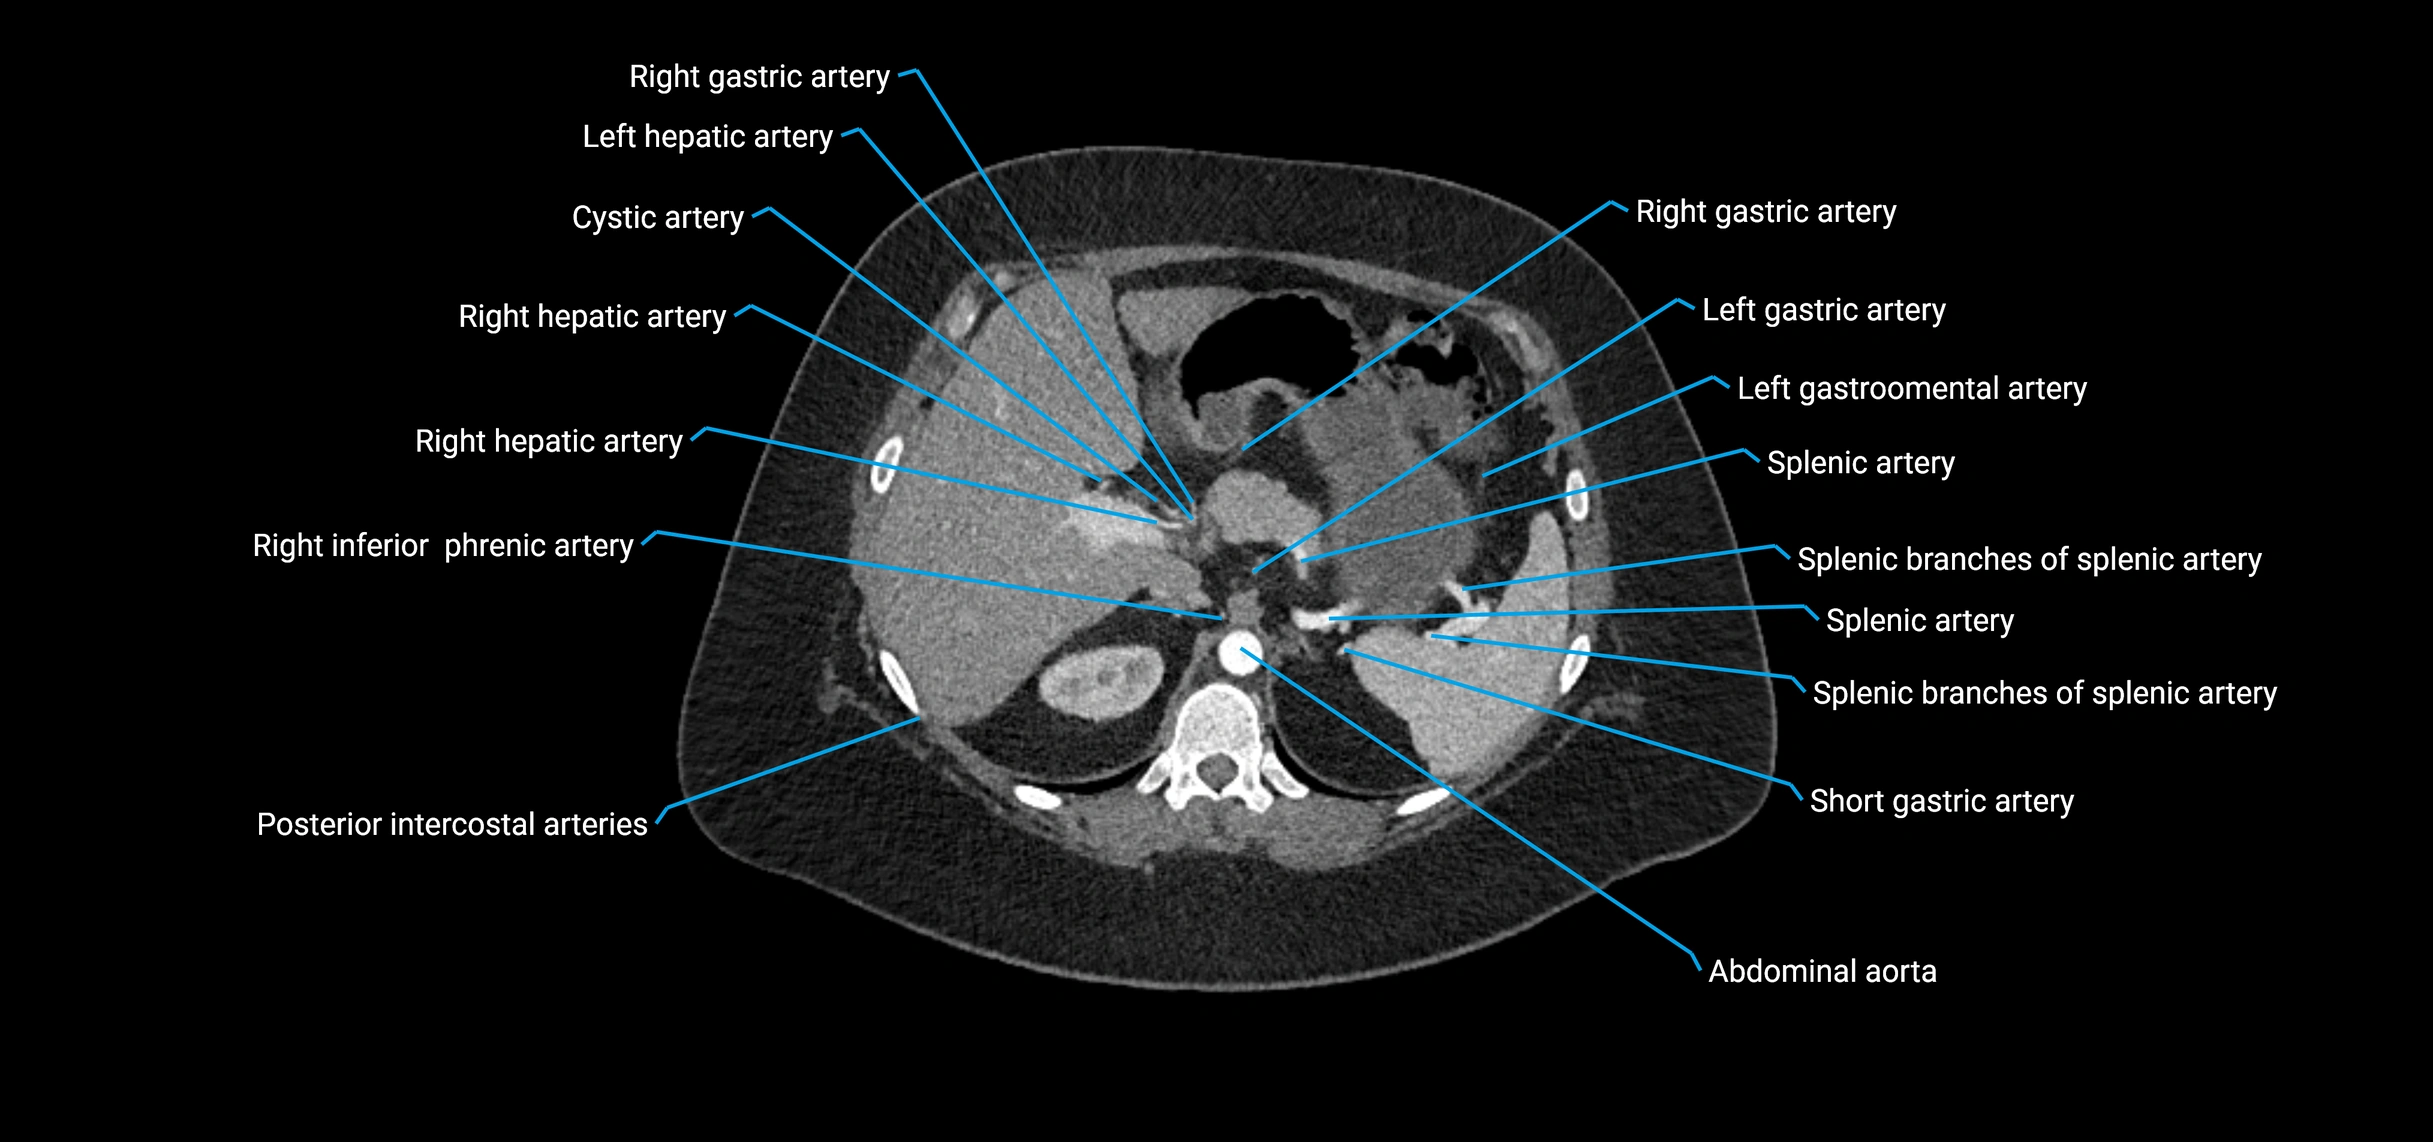

CT Appearance

Non-contrast CT:

• Appears as a tubular soft tissue structure anterior to vertebral bodies

• Calcified atherosclerotic plaques appear as hyperdense foci along the wall

• Useful for screening abdominal aortic aneurysm (AAA) size and mural calcification

Contrast-enhanced CT (CTA):

• Gold standard for abdominal aortic imaging

• Provides excellent detail of lumen, wall, aneurysm, thrombus, and branch vessels

• Multiplanar and 3D reconstructions help in aneurysm measurement, stent graft planning, and dissection evaluation

• Detects acute rupture, traumatic injury, or occlusion with high sensitivity

CT images

image